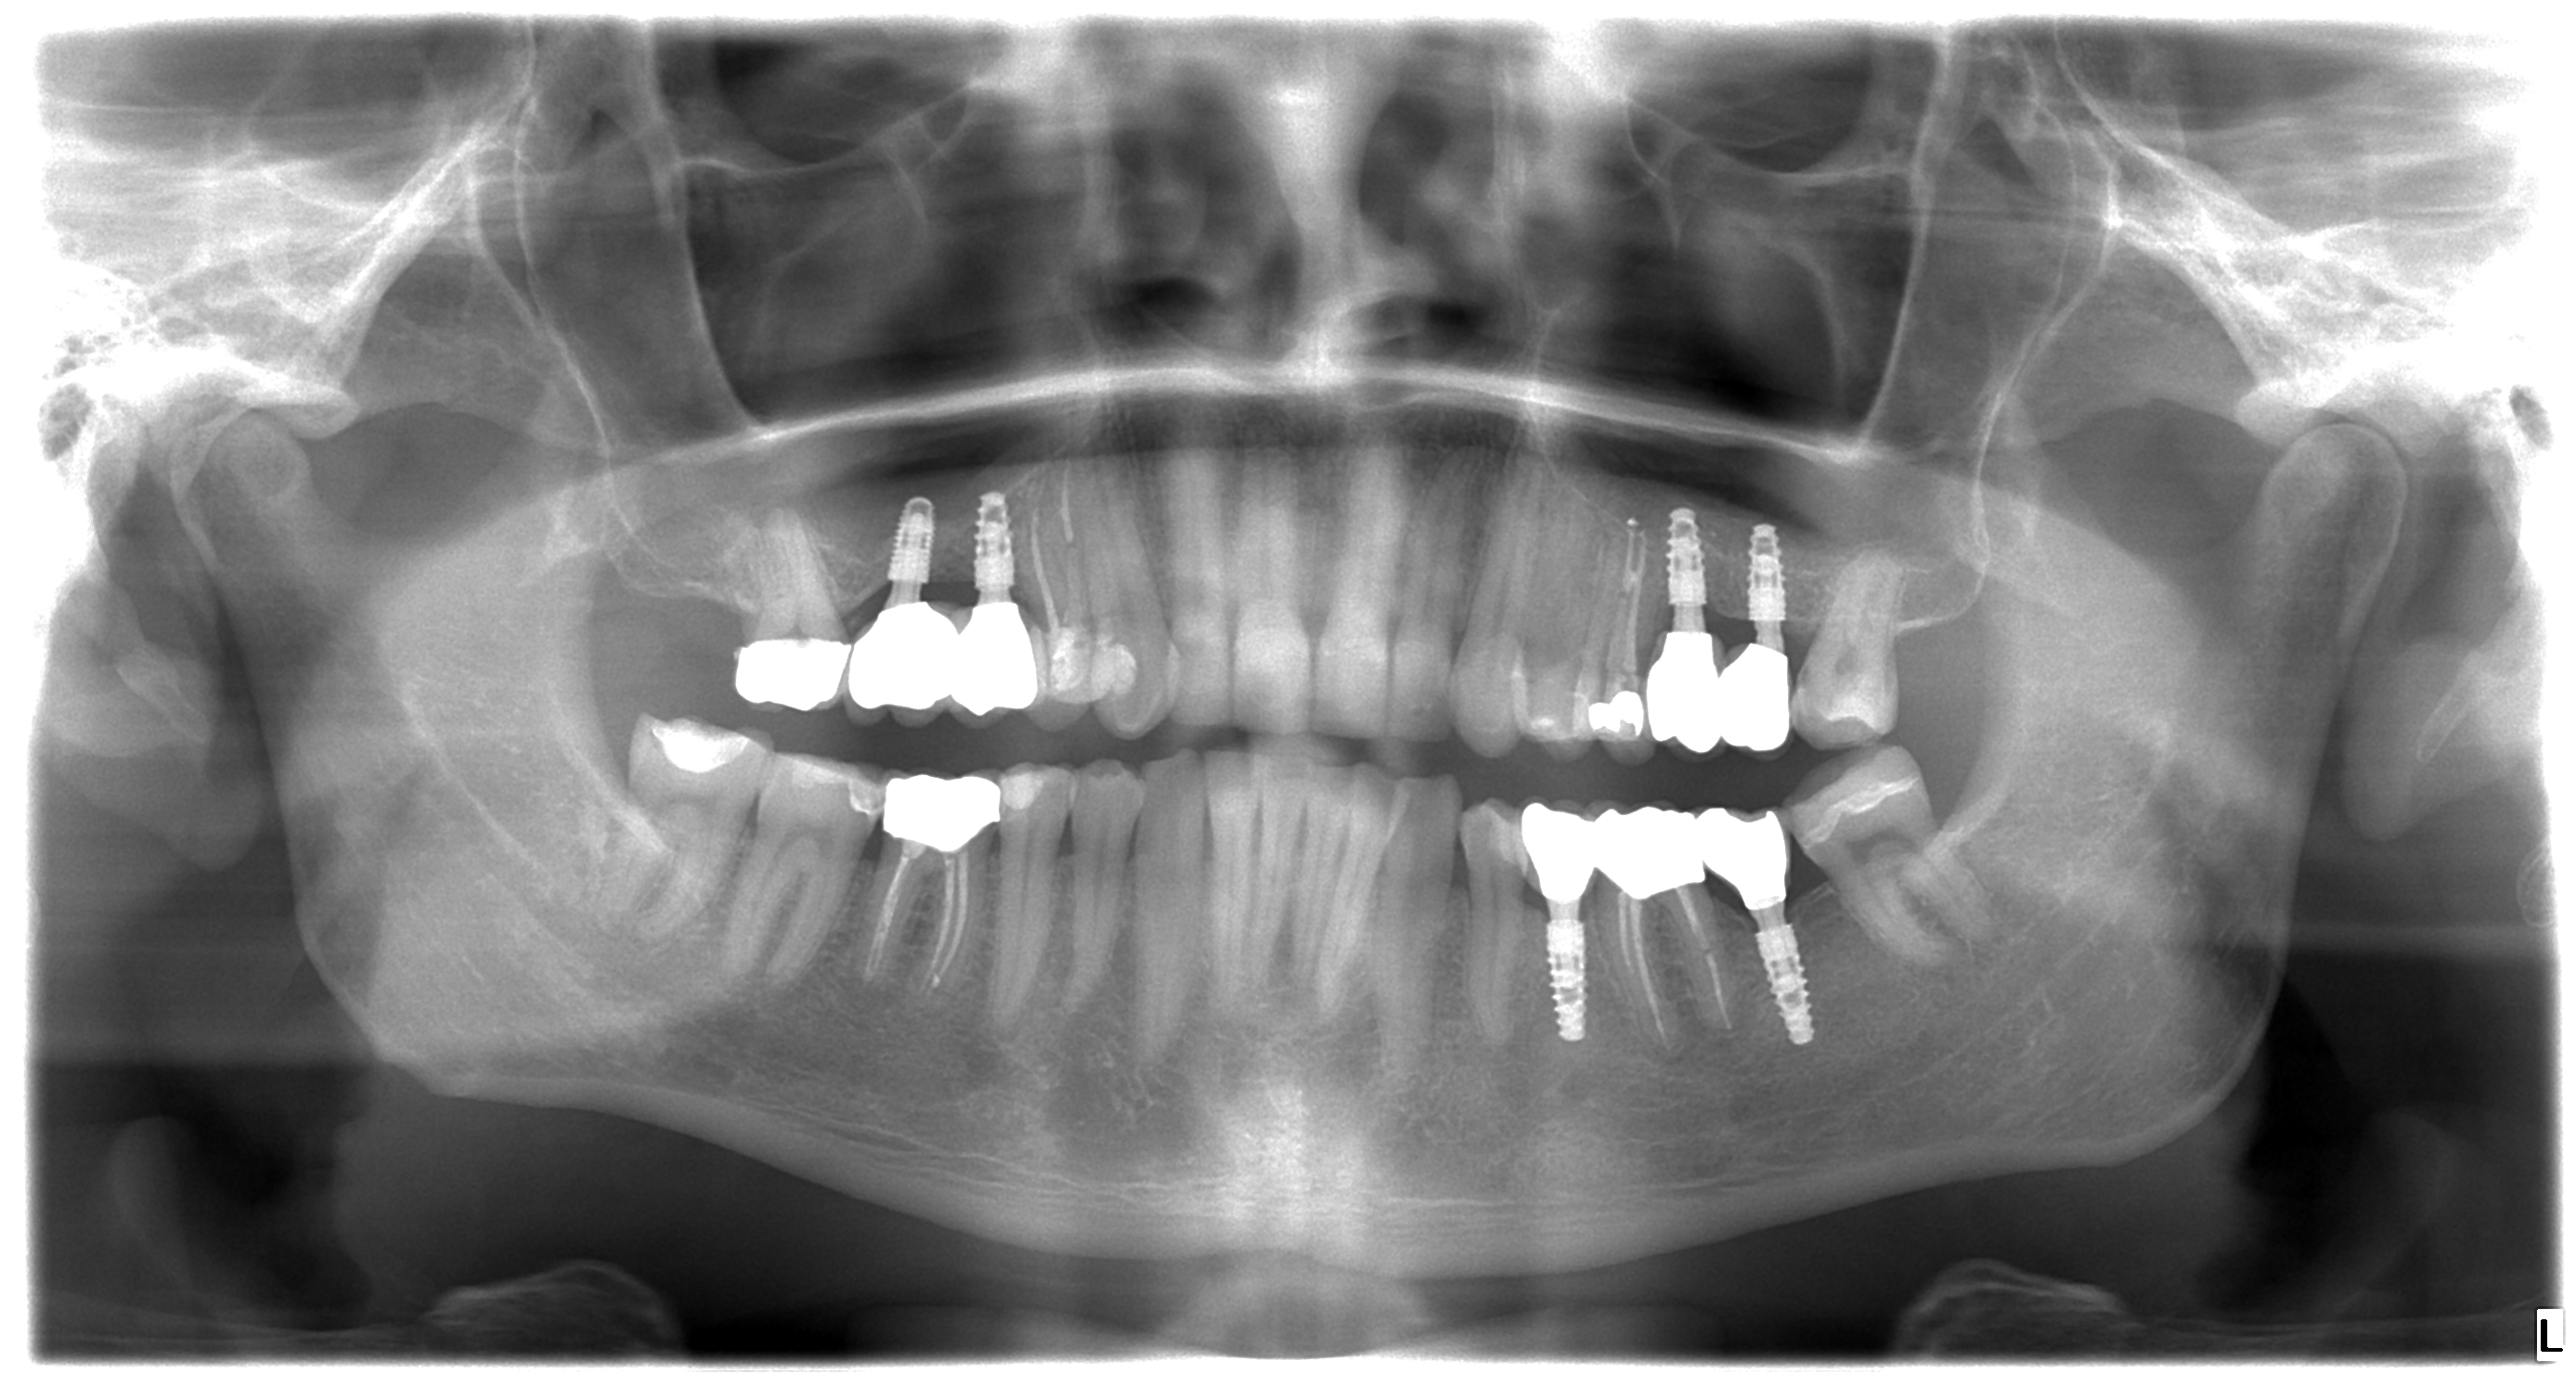

Patient´s X ray AFTER the treatment

Mr. Peter’s (32 years old) wish was to have nice and bright smile. Dr. Martin has made a treatment plan that contained 6 dental implants (4 for upper jaw and 2 for lower jaw), one tooth extraction, 5 re-root canal treatments and 12 dental crowns. After patient left examination room our staff discussed every detail of treatment with him and Mr. Peter made a booking for implant appointment with Dr.Martin in just 2 weeks after consultation.

The surgery began with the extraction of tooth number 26 and bone graft on upper jaw and it continued with implantation on 27, 26, 16 and 15 on upper jaw and 35 and 37 on lower jaw.

3,5 month after implantation Mr. Peter returned to our dental clinic to continue his treatment with four re-root canal procedures. Doctor decided to gave the implants more time for healing so patient returned in 2 months to get his front natural teeth reshaped and get impressions for his future implant crowns and zirconium dental crowns.

After next visit Mr. Peter left our clinic with this beautiful and natural looking smile. His upper jaw was fully reconstructed using dental implants in combination with dental crowns. Lower jaw was treated with 2 dental implants and two zirconium dental crowns.